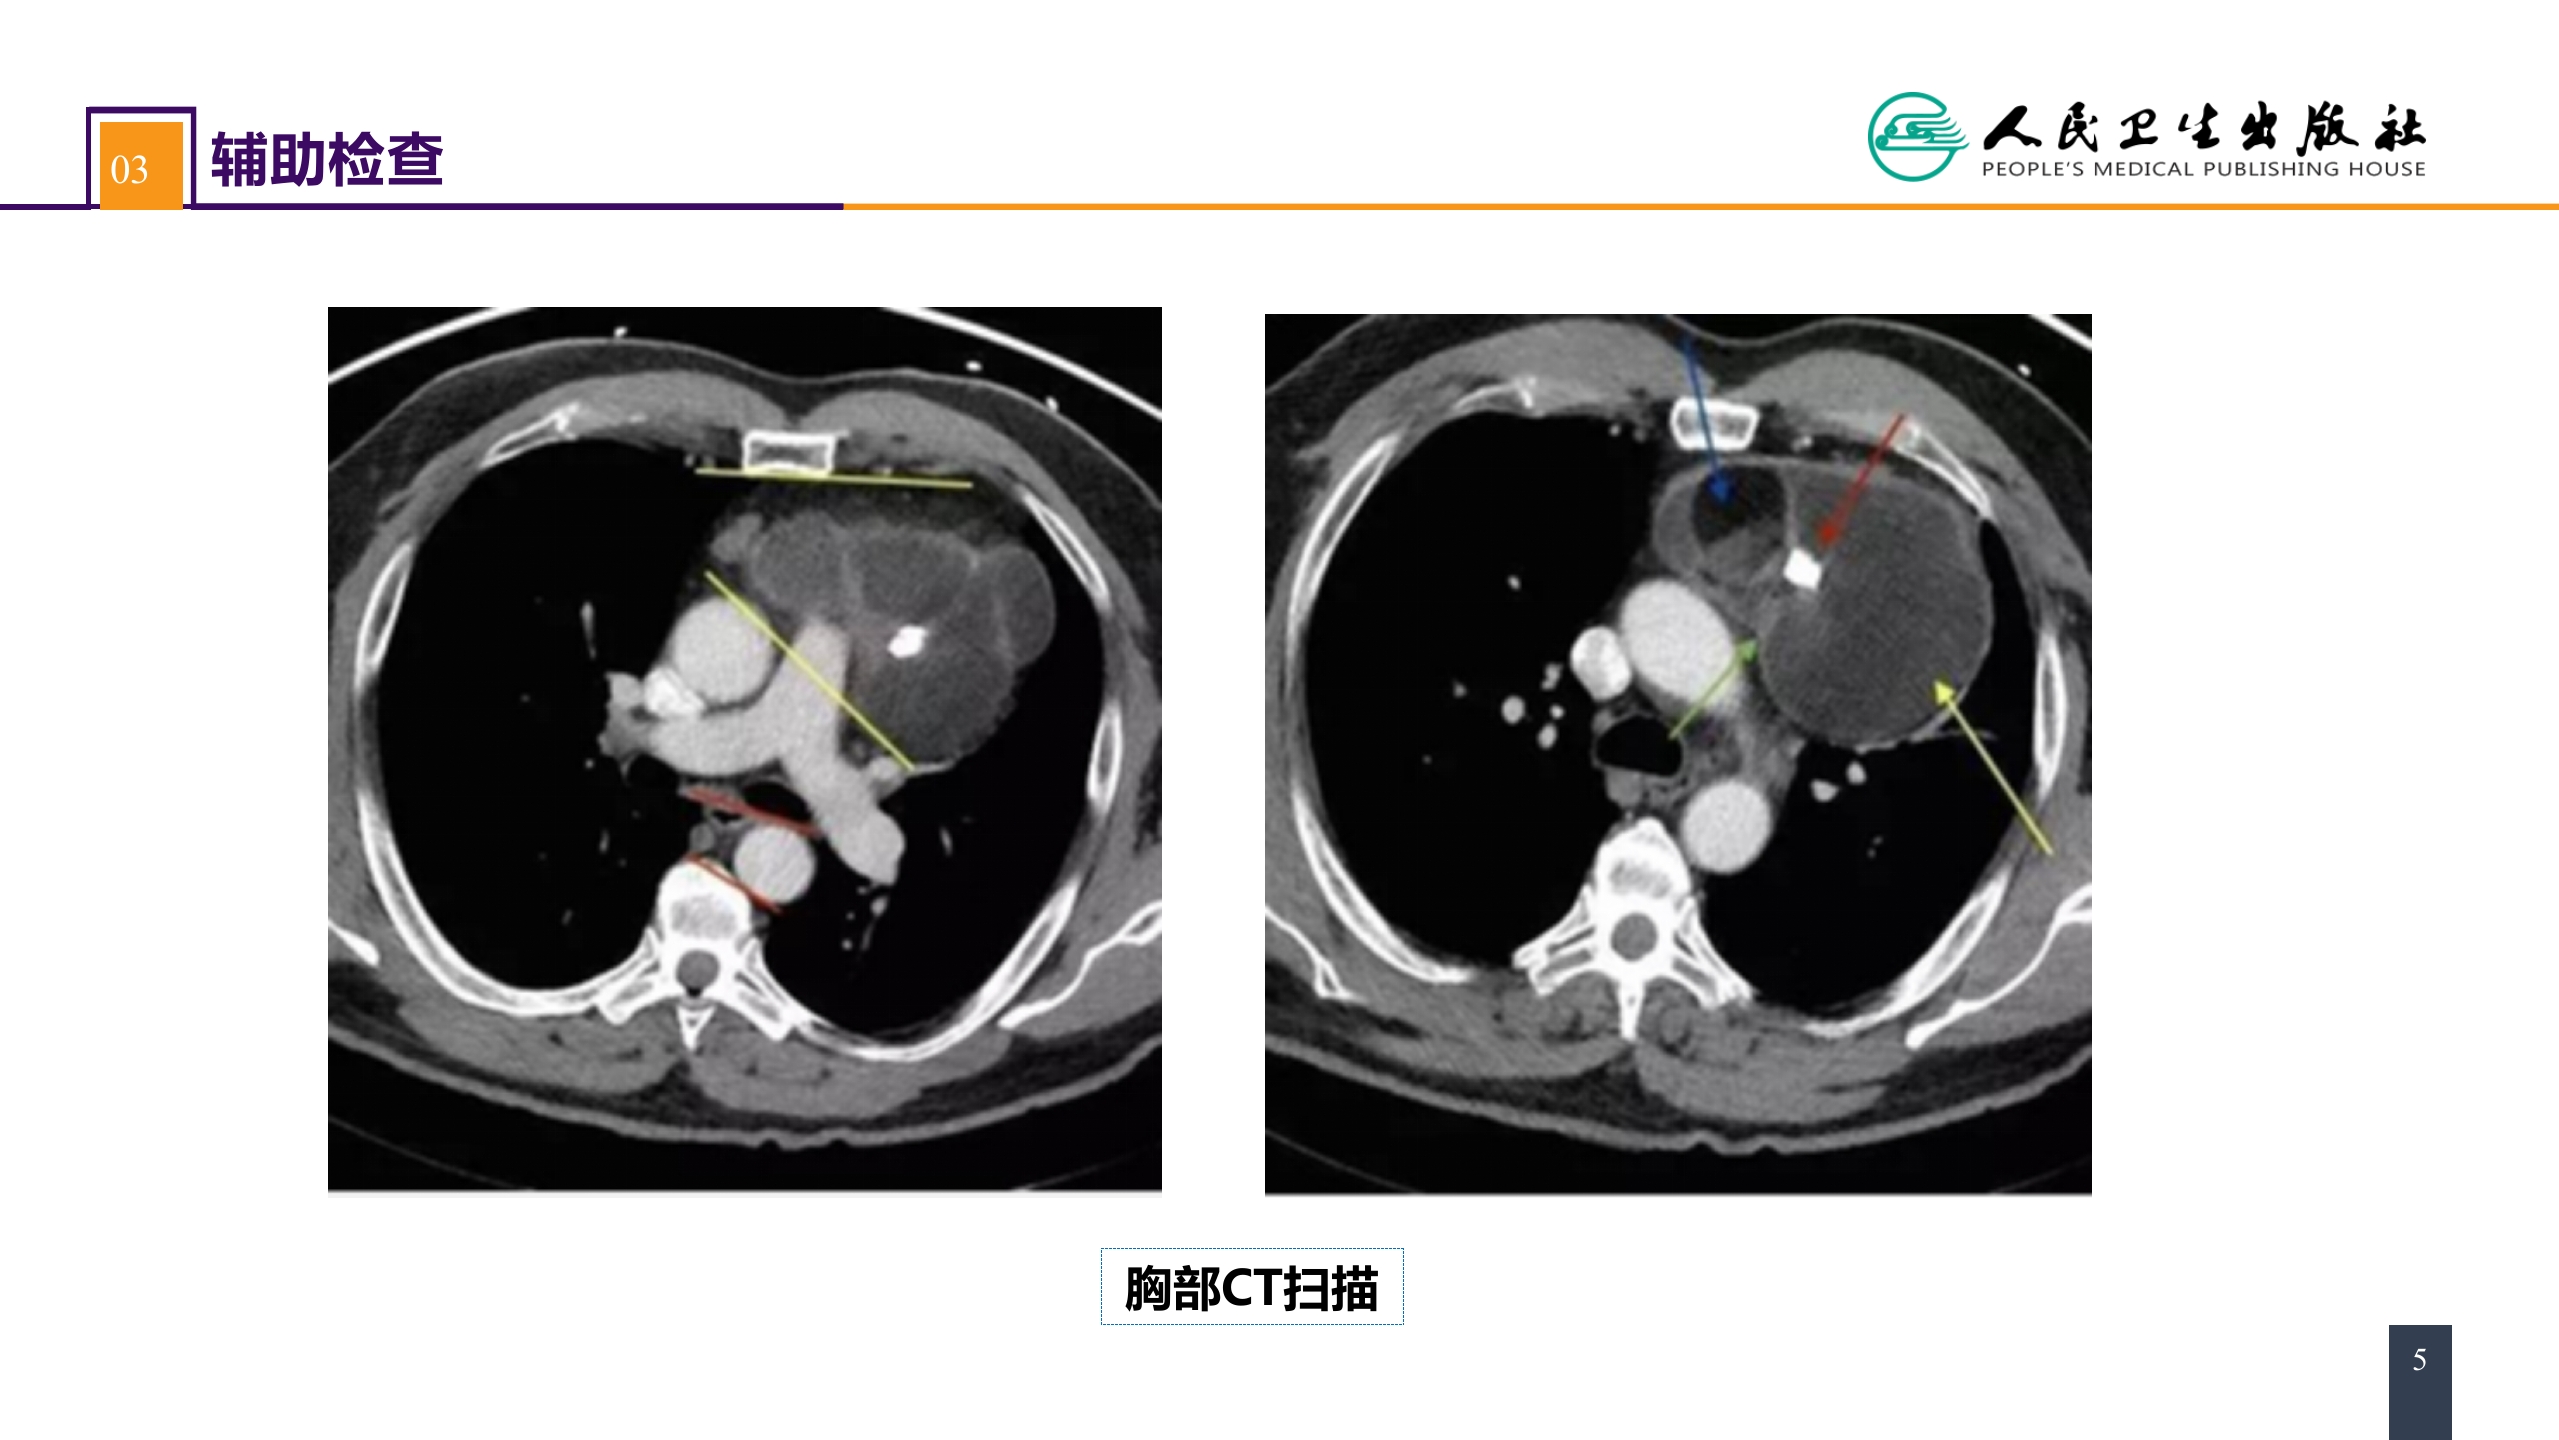

第二十八章 原发性纵隔肿瘤 案例分析-纵隔畸胎瘤